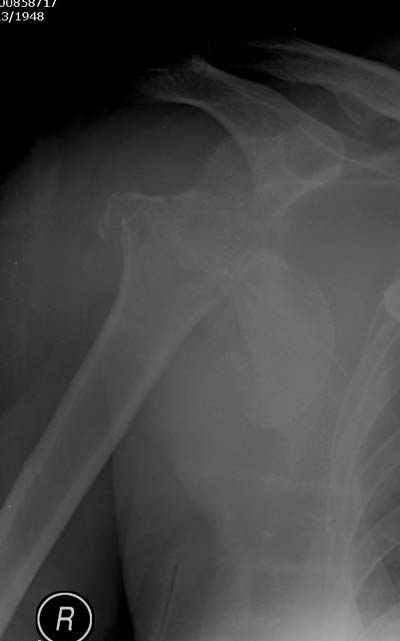

Здесь случай перелома-вывиха плеча, больному 56 лет, после "дважды" закрытой неудачной репозиции, опять же ургентно взяли в операционную, после полного общего обезболивания попытались сделать репозицию, и фиксацию провели спицами.

Казалось бы обычный перелом хирургической шейки плеча, с которыми нередко приходится сталкиваться (4-6% по статисткие) в жизни и у каждого травматолога тактика лечения не вызывает сомнения....

Сегодня взял больного повторно в операционную, не скажу, что повторная репозиция через неделю после первой попытки, была простая.

После удаления спиц попытался манипулировать отломками, но безуспешно, поэтому пришлось пользоваться периостальным элеватором, чтобы устранить смещение отломков и перепровести спицы. Проверил и перепроверил стабильность фиксации под ЭОПом, завтра Рг- будет готов, вот и поглядим....